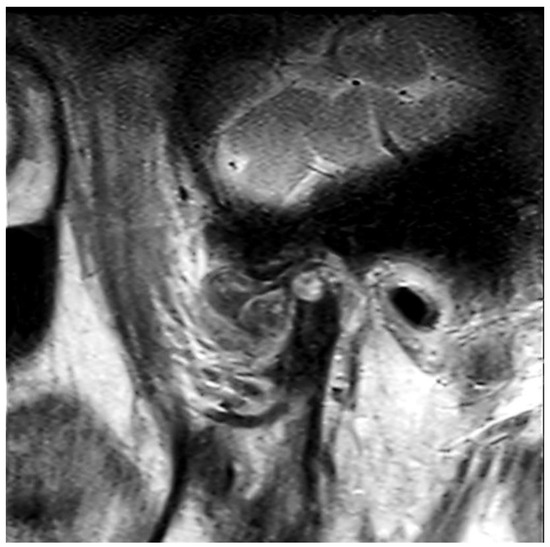

2. Case Presentation

2.1. Clinical Summary

2.2. Pathological Findings